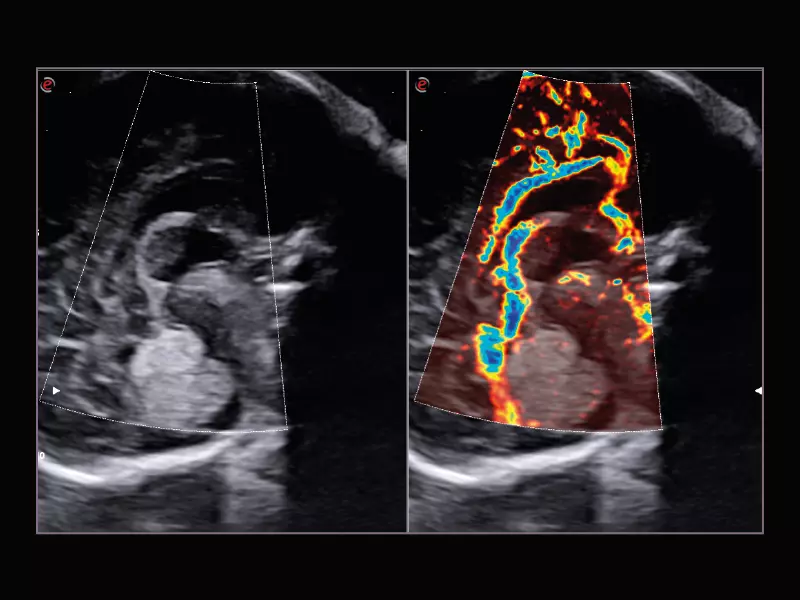

MyLab™9 Platform - Ultra-sensitivity Colour Doppler for precise visualization pulmonary veins

MyLab™9 Platform - Ultra-sensitivity Colour Doppler for precise visualization pulmonary veins

Q7 - Cardio CFM

Q7 - Cardio CFM

MyLab™A70 - Heart CFM

MyLab™A70 - Heart CFM